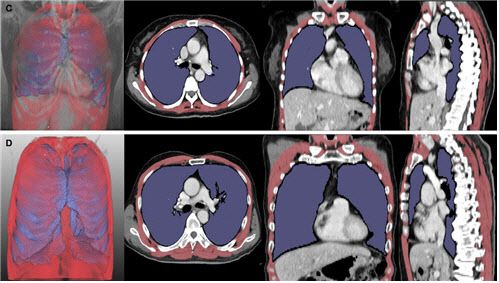

그러나 구강안면 근육이 약해져 구음장애(말과 발음이 부정확해지는 장애)가 동반된 환자는 이 검사의 정확도가 떨어져, 이를 대체할 새로운 호흡 기능 검사 방법이 필요했다. 이에 연구팀은 딥러닝 소프트웨어를 이용해 루게릭병 환자의 폐와 호흡근 위축 정도를 나타내는 폐 용적 지수(LVI)와 호흡근 용적 지수(RMI· 폐 및 호흡근 부피(㎤)를 키의 제곱(㎡)으로 나눈 값)를 개발하고, 병기 및 생존 기간과의 연관성을 확인했다.

그 결과, 폐·호흡근 용적 지수는 병기(1~4기)가 증가할수록 유의미하게 감소했다. 또한, 이 지수들이 낮은 그룹은 높은 그룹 대비 폐와 호흡근 위축이 뚜렷한 것으로 나타나, 기관절개술 또는 사망에 이르는 시점이 빨랐다.

또한, 통계 분석에 따르면 폐·호흡근 용적 지수는 기존 폐활량 검사와 유사한 정확도로 환자의 예후를 평가할 수 있었다. 이 결과는 구음장애 환자만 분석한 경우에도 동일하게 나타나, 연구팀이 개발한 영상 기반 지표가 호흡 기능을 평가하기 어려운 루게릭병 환자에서도 폐활량 검사를 대체할 수 있는 가능성을 보여줬다.